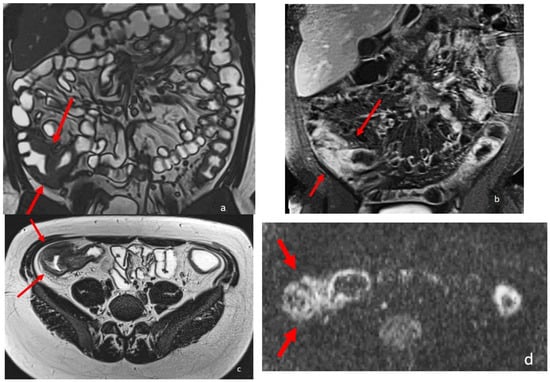

MRE is able to recognize intestinal Crohn’s disease inflammation with several inflammatory biomarkers, some of them well known and described for over three decades, such as mural thickening, wall edema on T2 weighted images, perivisceral edema, and post-contrast enhancement on T1-weighted images [2,8,9,10,11,12] (Figure 2). Recently, additional MRI biomarkers have also been evaluated, such as restricted mural DWI signal, number, size, and signal of lymphadenopathies, stratified and delayed wall enhancement, and fibrofatty proliferation [9,10]; overall, up to 13 different MRI biomarkers have been studied in the evaluation of chronic CD inflammation, with satisfactory results [7,8].

Figure 2.

An eighteen-year-old patient with Crohn’s disease; the arrows point to the wall involvement of the last ileal loop and caecum with wall thickening, post-contrast enhancement, and restricted diffusion. (a) is a coronal TrueFISP image; (b) is a coronal contrast-enhanced T1 weighted image; and (c) is an AxialT2 W high-resolution BLADE image. (d) Axial DWI b800.